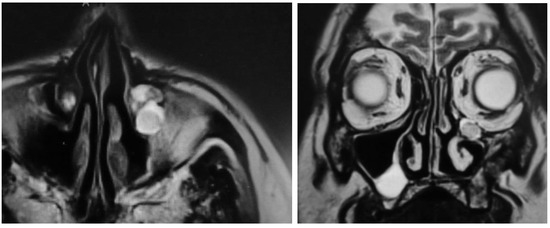

3.4. MRI